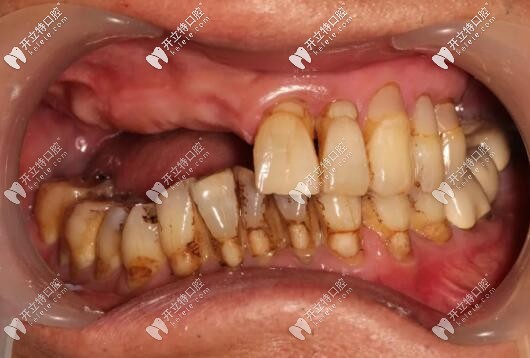

主訴:上頜活動義齒不適,重新修復(fù)。

修復(fù)前

病史上頜于10年前因牙周病導(dǎo)致的牙齒缺失,曾做過可摘戴活動義齒修復(fù)。